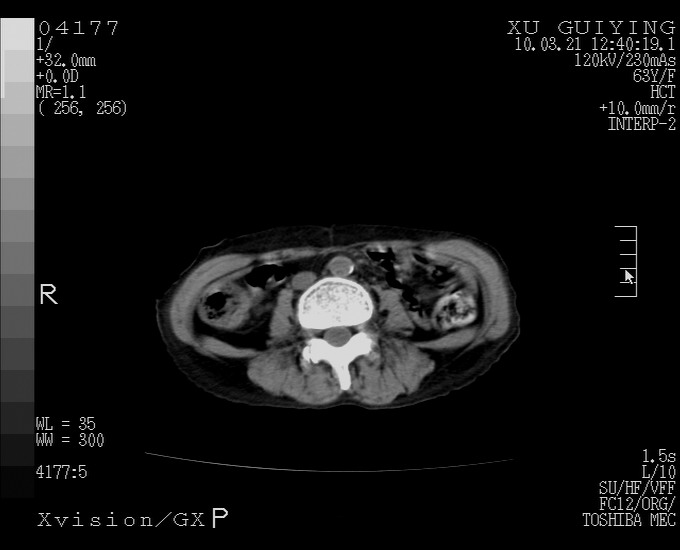

标题: CT25230:女,63岁,萎缩性胃炎病史,患者明显黄染,不能进 [打印本页]

标题: CT25230:女,63岁,萎缩性胃炎病史,患者明显黄染,不能进

胆囊体积增大,胃窦壁增厚

胆囊体积增大,密度不均匀,结石不除外;胃壁增厚,考虑胃癌,建议增强。

胆囊体积增大,密度增高,较均匀,外缘也较光滑,应考虑胆囊炎。因为胃未充盈,不好说壁增厚。肝左叶及脾门处见低密度灶,有可能是血管瘤,不排除囊肿。建议超声检查或强化。